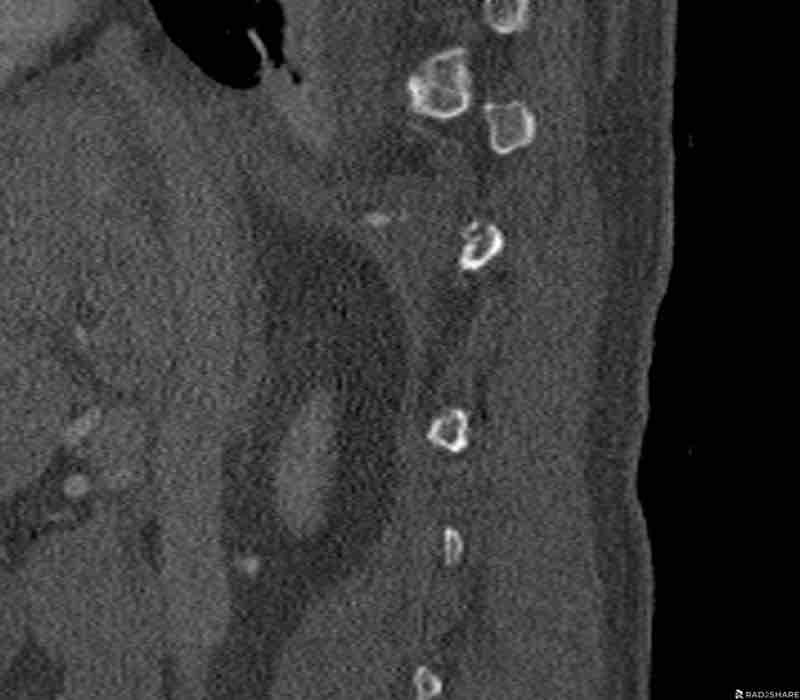

Scroll through the images.

What is the highest AO-type of injury?

Any additional findings?

Then continue with the next images…

Findings

- Black arrows: horizontal fractures through the pedicles as a result of flexion distraction trauma.

- White arrows: soft tissue swelling indicating injury to posterior ligaments.

- Circle: compression fracture of posterior wall (2 points) and two endplates (2 points)

Conclusion

Type B2-A4

Flexion distraction injury with separation on the posterior side and a secondary burst fracture involving both endplates and the posterior wall.